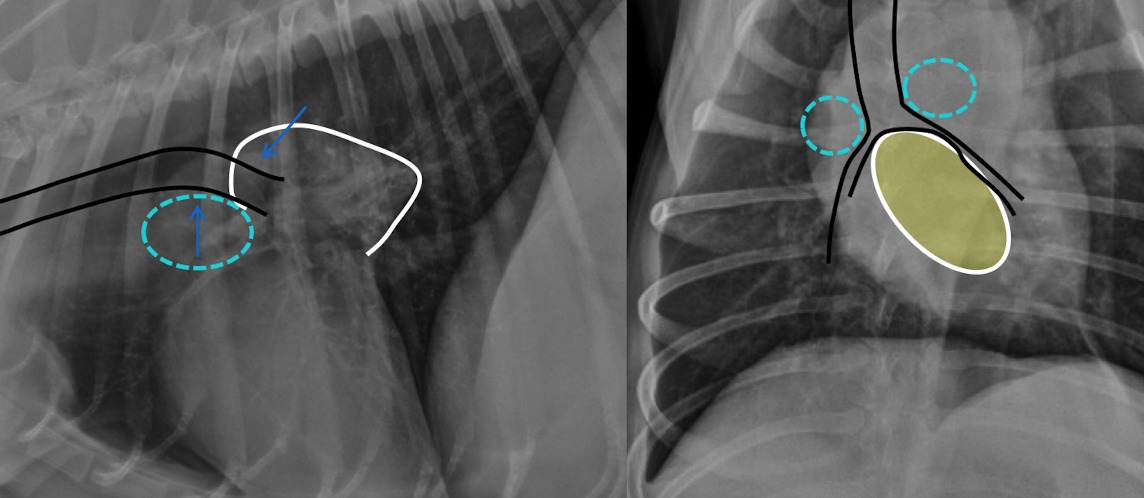

which one pulmonary mass vs extrapleural sign

what is this showing

left: enlargment of middle tracheobronchial Lymph node → ventral displacement of carina

right: left atrial enlargmentdorsal displacement of carina

both will show bowing of the mainstem bronchi on VD (cowboy) and double opacity sign